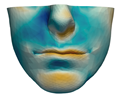

| M1 |  |  |  |  |  |  |

| M2 |  |  |  |  |  | |

| M3 |  |  |  |  |  | |

| M4 |  |  |  |  |  | |

| M5 |  |  |  |  |  |

| M6 |  |  |  |  |  |  |

| M7 |  |  |  |  |  | |

| M8 |  |  |  |  |  | |

| M9 |  |  |  |  |  | |

| M10 |  |  |  |  |  |